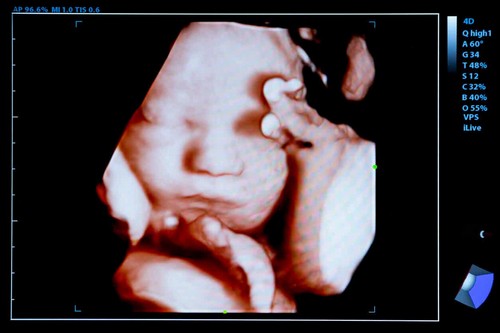

4. Ultrasuoni 3D e 4D

Citiamo queste due tipologie in una sezione apposita, vista la grande popolarità che hanno riscosso negli ultimi anni.

Ma al di là della possibilità che offrono di vedere nel dettaglio il viso del bambino, la sua reale utilità è discussa da alcuni specialisti.

Gli ultrasuoni 3 e 4 dimensionali consentono una migliore visualizzazione del feto e rilevano alcune malformazioni, ma ciò non implica che si possa fare una diagnosi precoce delle sindromi congenite.

Sono necessari più strumenti per corroborare determinati risultati e questo problema non è così semplice.

In generale, l’ecografia 3D consente di ottenere un’immagine tridimensionale del feto e la 4D aggiunge movimento ad essa.

Attraverso quest’ultimo è possibile vedere il bambino vivere e dirigersi all’interno del grembo materno.